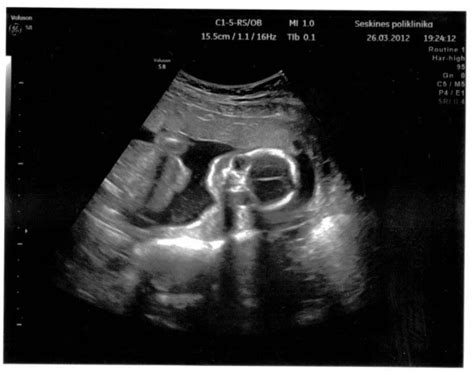

Nėštumo laikotarpiu svarbu turėti išsamią informaciją apie vaisiaus echoskopiją, kada ji atliekama, ką parodo, kokie yra 2D, 3D, 4D ir dopleriniai tyrimai, kraujotakos vertinimas ir saugumas. Taip pat svarbu žinoti apie makšties išskyras nėštumo metu: kada jos normalios, kada kelti aliarmą ir kaip tinkamai prižiūrėti intymią higieną. Nėštumo testai ir neaiškūs rezultatai, tokie kaip „vaiduokliukas“, reikalauja dėmesio ir informacijos.